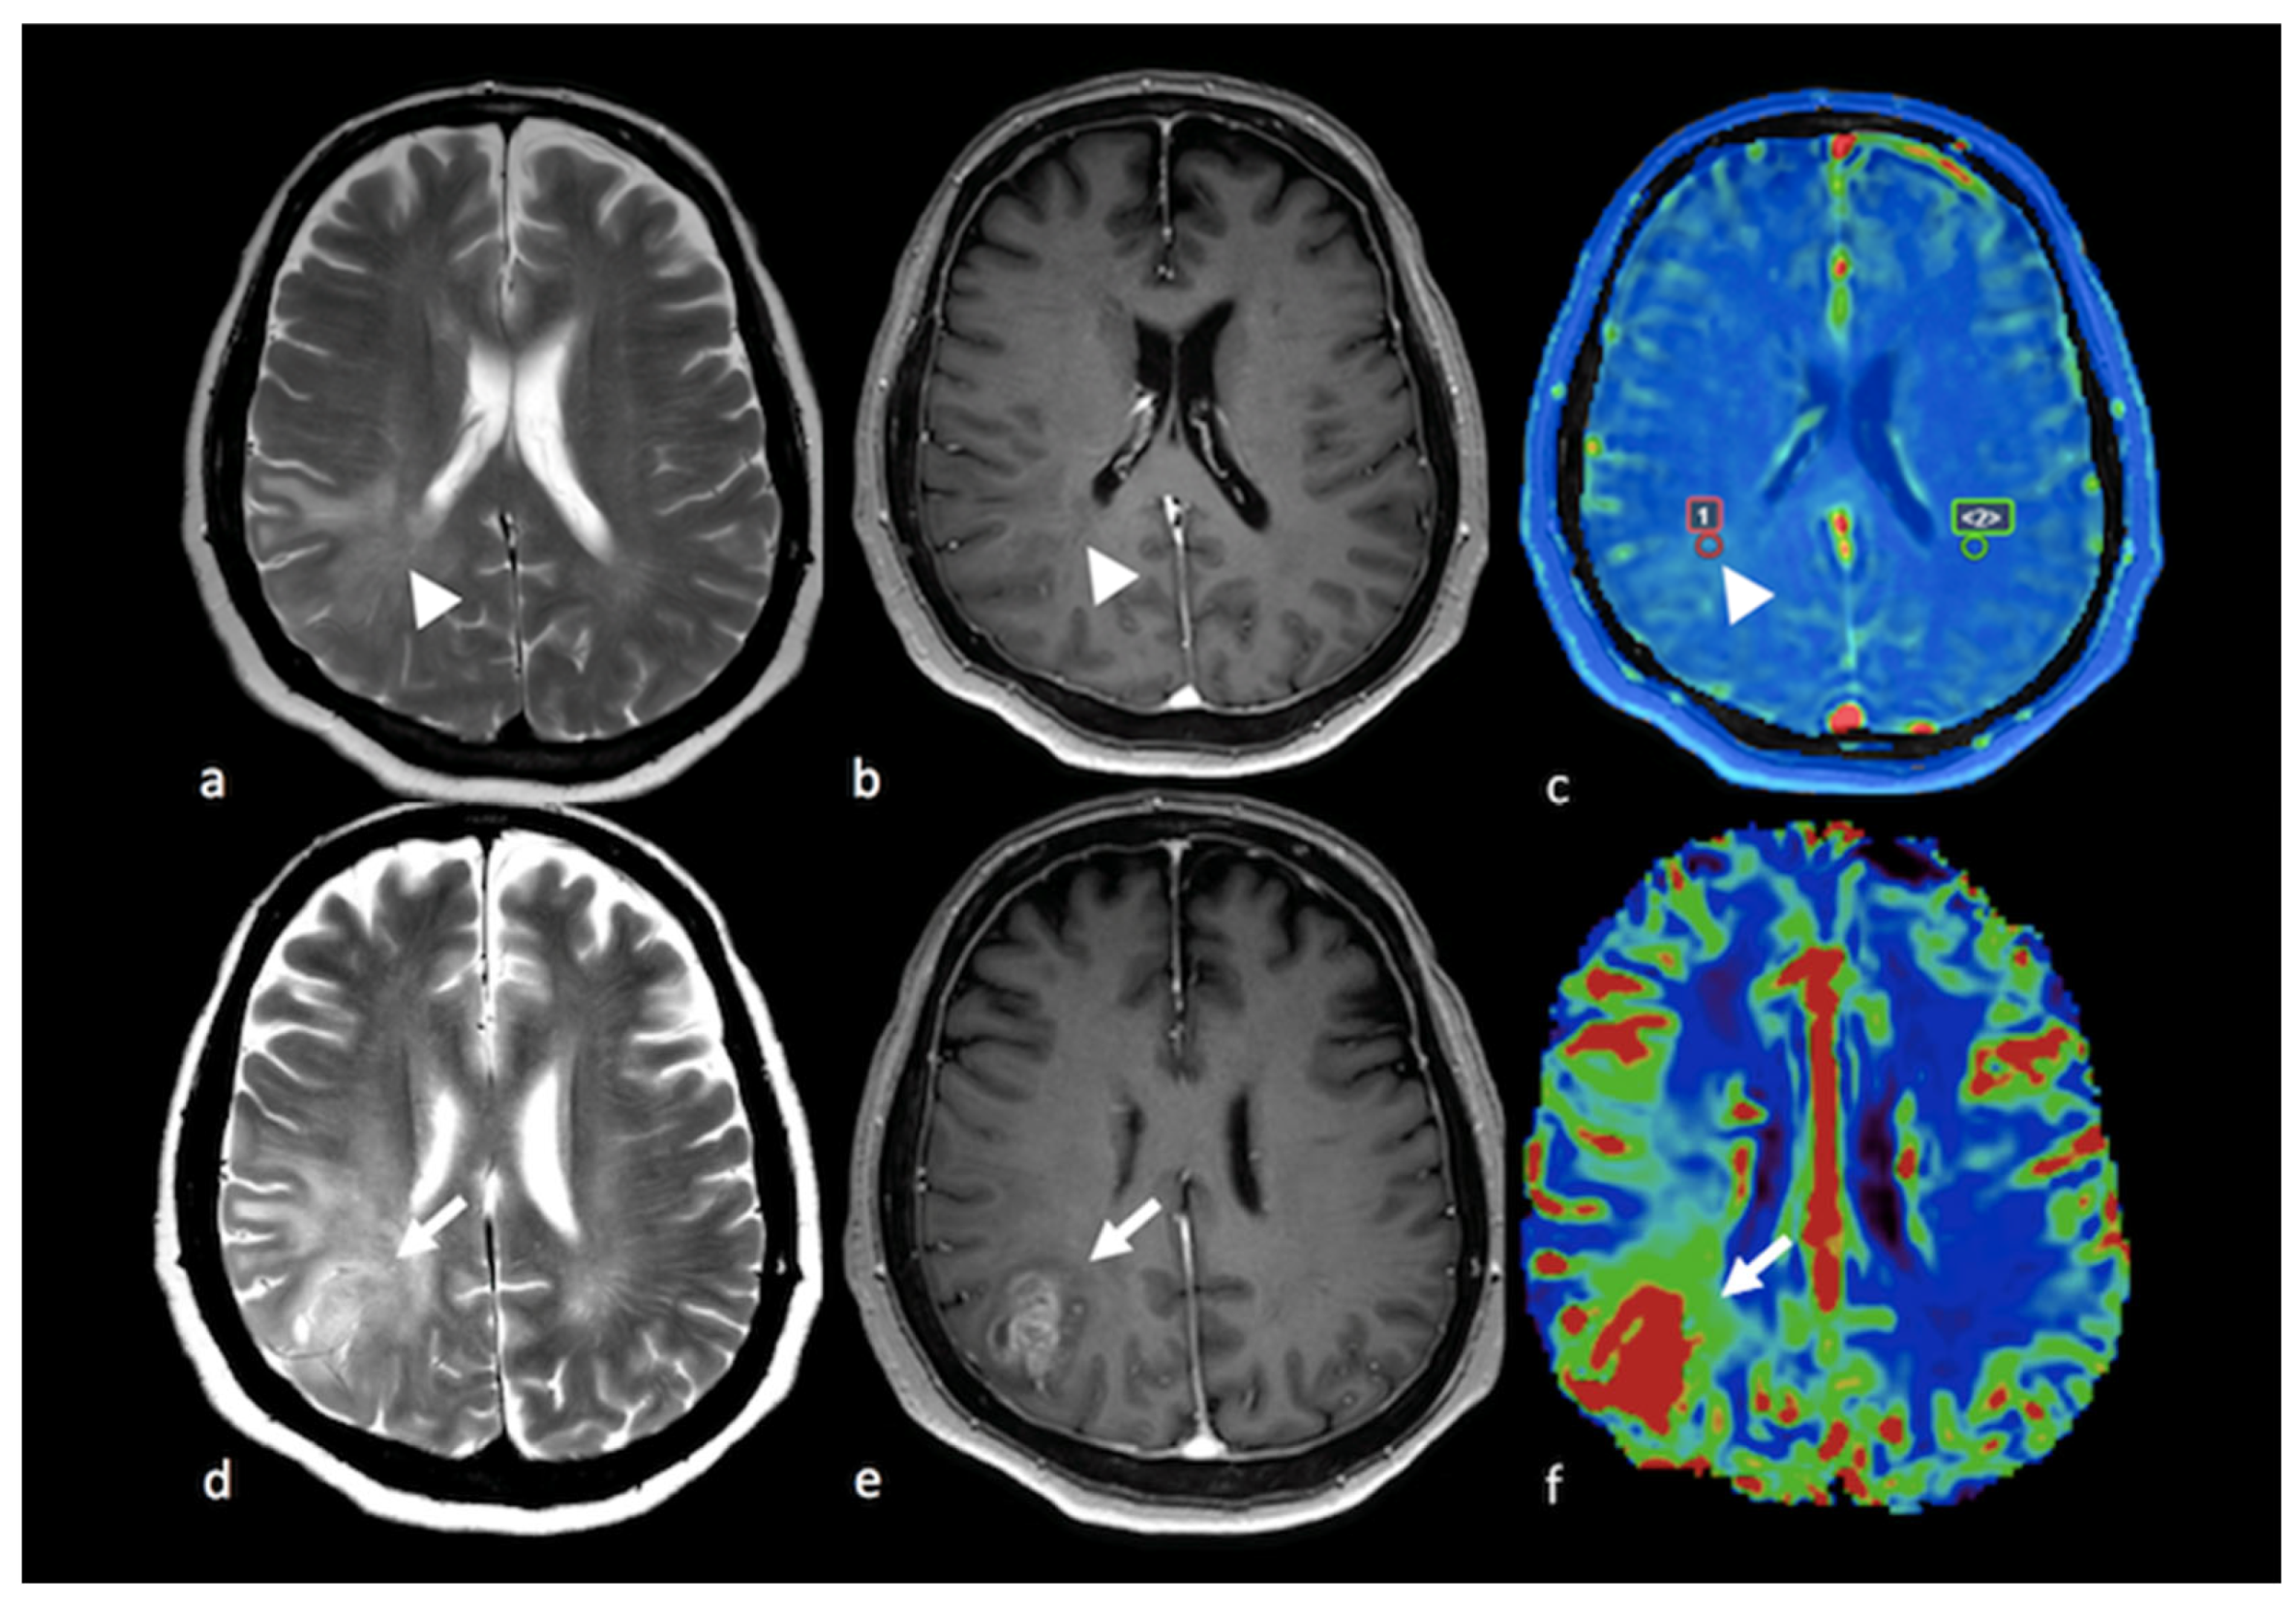

3.5. Amide Proton Transfer

- Dasgupta, A.; Geraghty, B.; Maralani, P.J.; Malik, N.; Sandhu, M.; Detsky, J.; Tseng, C.L.; Soliman, H.; Myrehaug, S.; Husain, Z.; et al. Quantitative mapping of individual voxels in the peritumoral region of IDH-wildtype glioblastoma to distinguish between tumor infiltration and edema. J. Neurooncol. 2021, 153, 251–261. [Google Scholar] [CrossRef]